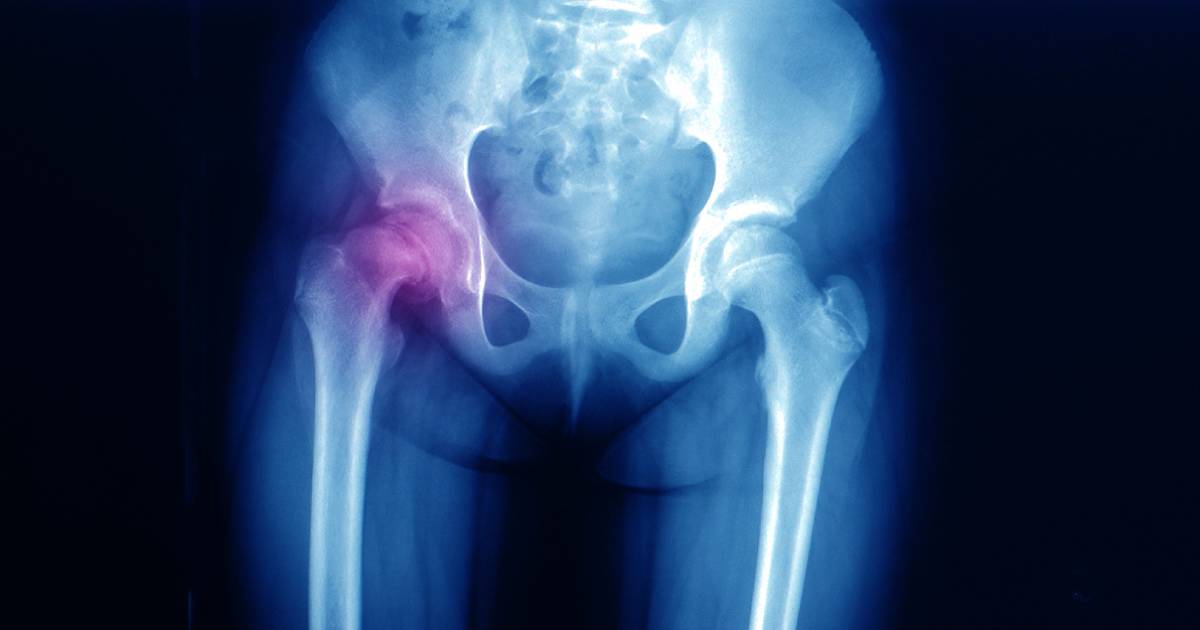

Hip pain in children requires careful evaluation to rule out serious underlying causes like transient synovitis or Perthes disease. Learn about the mechanical and systemic symptoms to watch for, and explore our non-invasive management options—including gait correction and custom orthotics—designed for growing bodies.

Juvenile hip pain and discomfort can arise from musculoskeletal injuries, developmental conditions, or infections. Examples of such conditions include:

- Imaging technologies such as X-ray and diagnostic ultrasound to evaluate the structures and alignment of the lower limbs, as well as the severity of the condition.